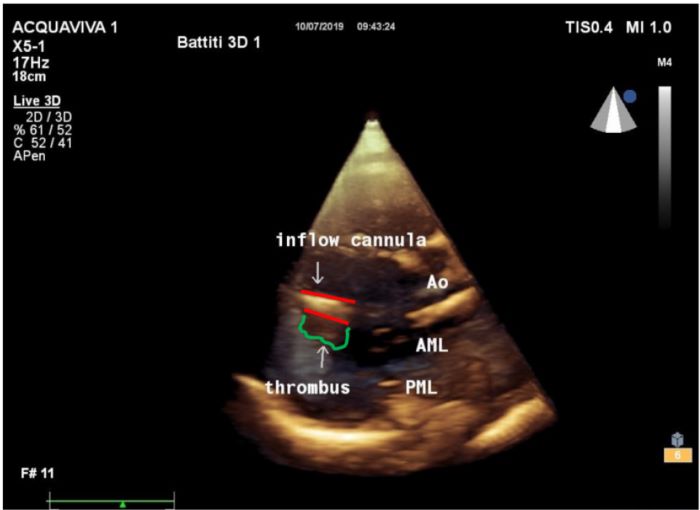

At the time of thrombosis, in eight cases out of 17 (47%), thrombi were detected in the left ventricle lining the outer surface of the inflow cannula without wedging into its lumen. No clots were detected after thrombolytic treatment. Figure 3 shows a three-dimensional apical transthoracic view with a thrombus attached to the bottom side of the inflow cannula.

With regard to echocardiographic findings, our series support once more the pivotal role of echocardiography for the detection and management of HVAD thrombosis, as demonstrated by several authors previously[1,5,11,12,15]. The assessment of the correct position of the inflow and outflow cannula was achieved. Despite quantification of blood flow velocity at the site of the inflow cannula within the left ventricle is reported difficult to record due to artefacts around the cannula[11], the alignment of the echo probe to the inflow cannula describing an angle < 20° allowed assessment of increased flow velocities. These are an indirect sign of pump obstruction. Moreover, the addition of transthoracic three-dimensional modality identified, in eight cases out of 17 (47%), thrombi lining the outer surface of the inflow cannula without edging into the lumen. Detection of thrombi shed a light on the likely mechanism of HVAD thrombosis: formation of clots occurs in the left ventricle in areas close to the inflow cannula, flow turbulence triggers the fragmentation of clots into debris that easily migrate into the impeller of the device through the inflow cannula, and, as a result, the device increases the energy consumption.